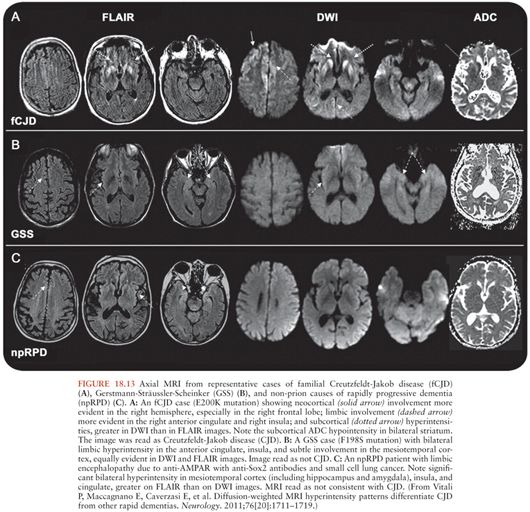

9 Prion diseases and rapidly progressive dementias Neupsy Key Holes In The Matter A Case Of Prion Disease Answer Key Bovine spongiform encephalopathy, also known as mad cow disease, is a progressive neurological disorder of cattle; A few week later, newspaper reported called asking about the prion contamination; What did they wanna know? Teaching notes & answer key. Which prion disease was the most likely to have been contracted by the people in this story? The prion disease that was. Holes In The Matter A Case Of Prion Disease Answer Key.

Brain MRI findings in prion disease. (a) Axial DWI imaging showing a Holes In The Matter A Case Of Prion Disease Answer Key Devin maughn holes in the matter: Know the symptoms and diagnosis of prion diseases. A few week later, newspaper reported called asking about the prion contamination; Which prion disease was the most likely to have been contracted by the people in. The prion disease that was likely to affect the people in this story is. Teaching notes & answer key.. Holes In The Matter A Case Of Prion Disease Answer Key.